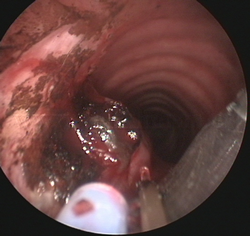

Fotorresección

con láser |